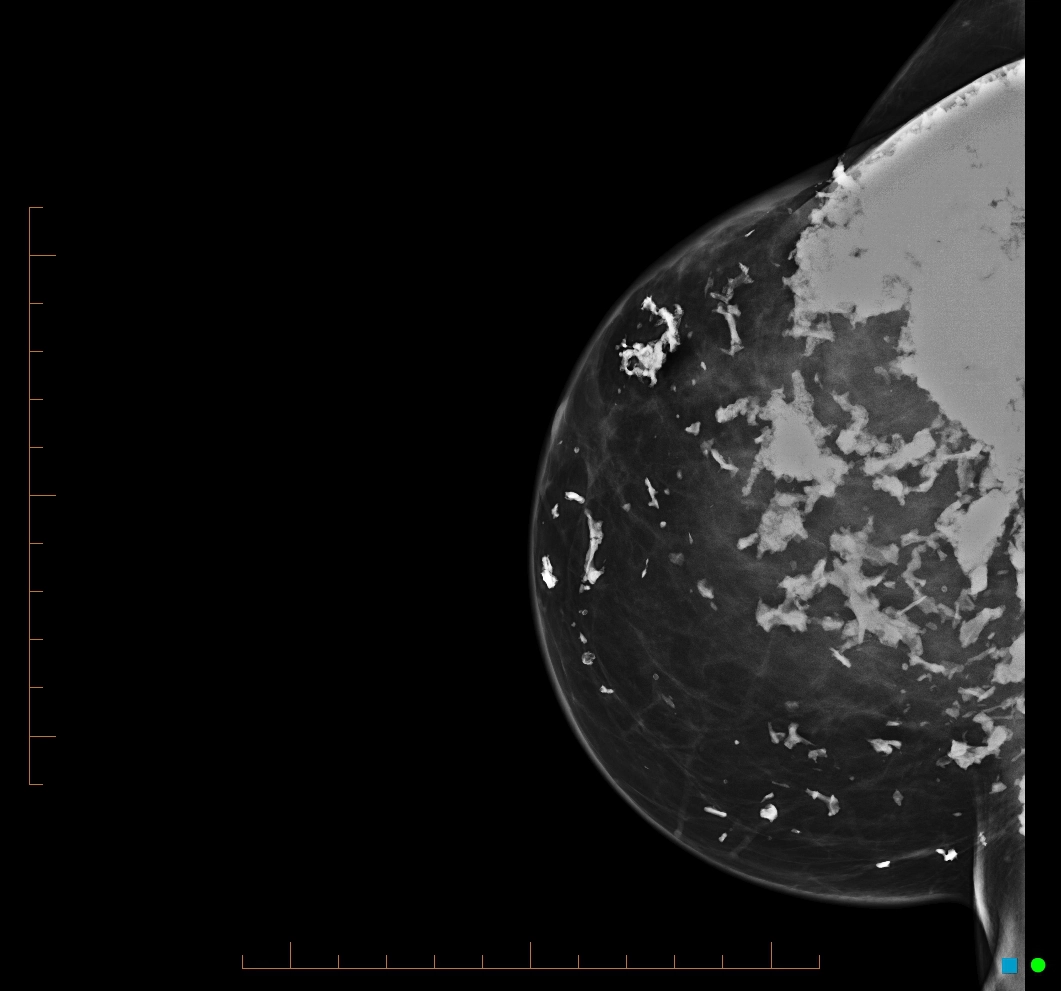

Vôi hóa tuyến vú (Breast calcifications)

Vôi hóa lành tính

Vôi hóa dạng bắp rang (Popcorn-like calcification of the breast)

Vôi hóa loạn dưỡng (Dystrophic calcification within the breast)

Vôi hóa nghi ngờ

Vôi hóa nghi ngờ ác tính ở vú (Suspicious breast calcifications)